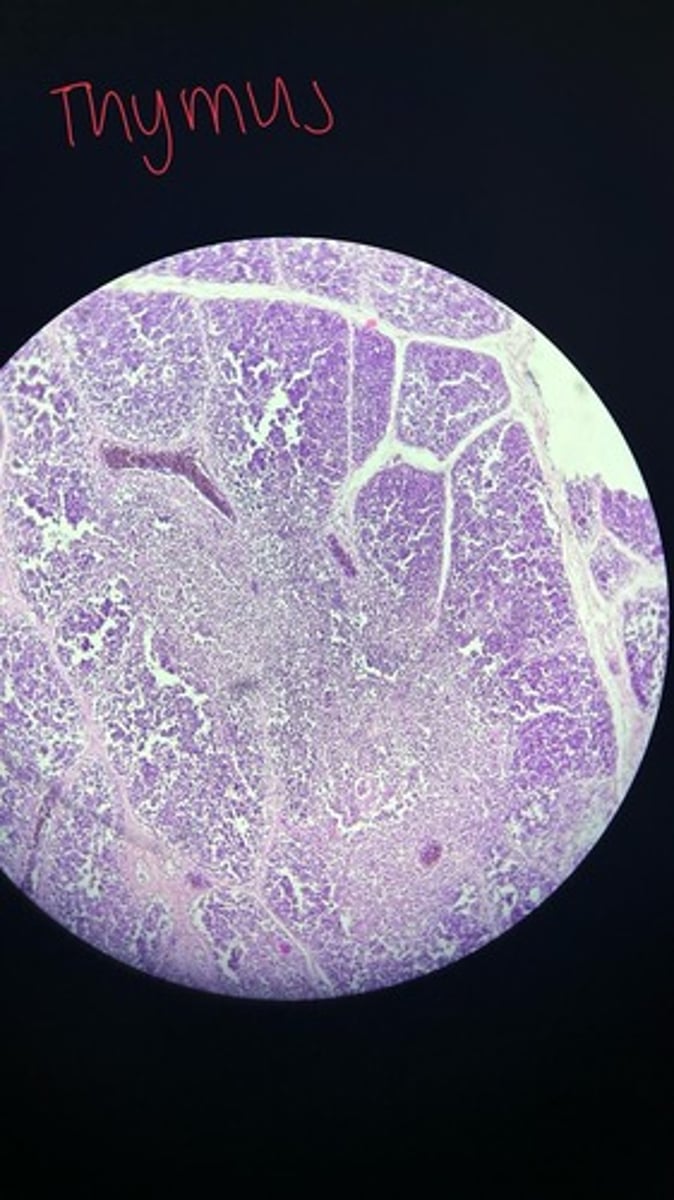

Thymus HE

Thymus HE

Thymus HE

Thymus HE

Thymus HE

Thymus HE

Thymus HE

Thymus HE